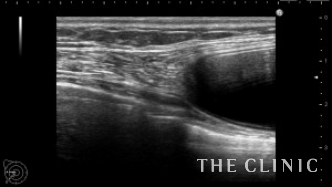

18年前にバッグを挿入していましたが、カプセル拘縮が強く皮膚の引き攣れがありました。エコー画像です。バッグは大胸筋下に挿入されています。

シリコンバッグによるカプセル拘縮のエコー診断カルテ